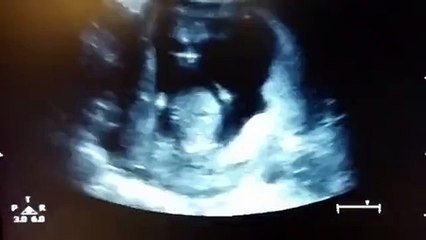

استشارية نساء وولادة توضح كيفية تأجير رحم وعملية وضع جنين بداخله